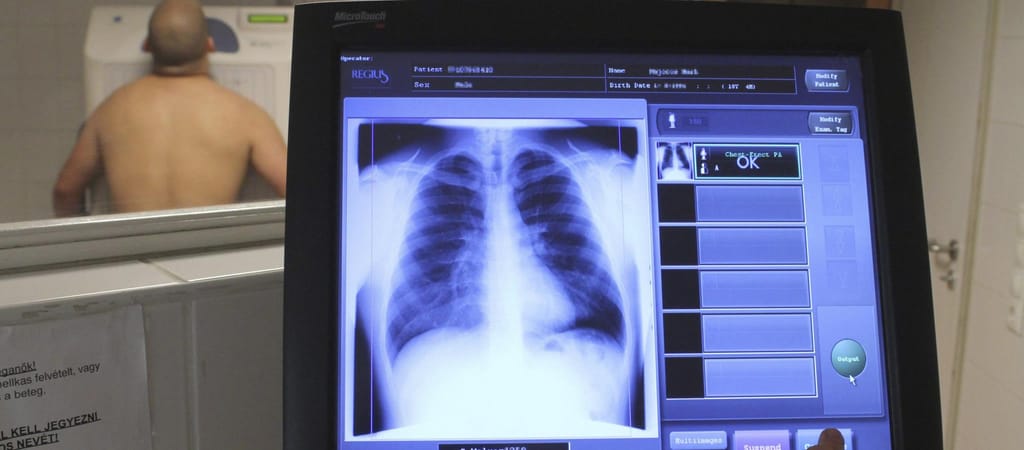

Az Oxfordi Egyetem által használt módszer a hagyományos vizsgálatok által nem látható elváltozásokat is képes azonosítani.

Az Oxfordi Egyetem eljárásának lényege, hogy a betegek az MRI-s vizsgálat során xenongázt lélegeznek be.

Ez egy színtelen és szagtalan gáz, és képes “megvilágítani” a tüdő különféle pontjait. A tudósok nem gondolták, hogy a koronavírusos betegeknél is bevethető, de nemrég kipróbálták. Az eljárást olyan pácienseknél tesztelték, akik korábban covidosok voltak, és még hónapokkal a fertőzöttségük elmúlása után sem gyógyultak meg teljesen.

A BBC szerint a kutatók összesen tíz, 19 és 69 év közötti betegen próbálták ki az újfajta letapogatási technikát. Nyolc esetben a tüdő elváltozásával kapcsolatos jeleket azonosítottak, olyan elváltozásokat,

melyeket a hagyományos vizsgálatok nem tudtak kimutatni.

A szkennelési megoldást kidolgozó Fergus Gleeson professzor most szeretné kiterjeszteni a vizsgálatot legalább 100 emberre, mert feltételezhető, hogy esetükben is találnak majd valamit, ami a tüdő károsodására utalhat. A szakember úgy véli, hogy a xenon által azonosított elváltozásoknak köze lehet a Covid hosszú távú lefolyásához.